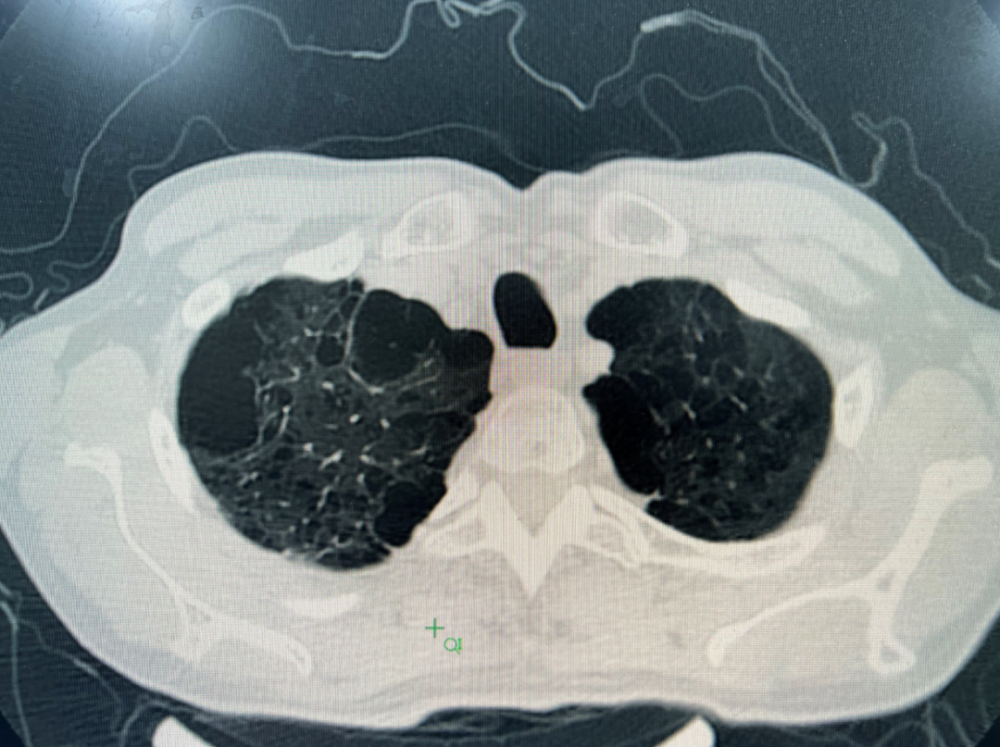

横断面:显示肺内两个紧邻的肺大泡.

纵膈面也看见胸膜下肺大泡.